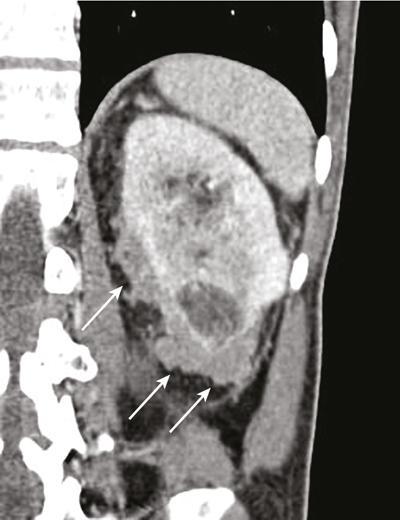

IMAGING OF RENAL MALIGNANCIES IN ADULTS Aparna Katdare, Palak Bhavesh Popat, Nilesh P. Sable, Ganesh Bakshi, Suyash Kulkarni Detection of renal masses has increased remarkably in recent times owing to wide-spread use of cross-sectional imaging. Imaging plays an important role in characterizing renal masses and is indispensable in treatment planning in renal malignancies. The most commonly encountered malignant renal masses in practice include renal cell carcinoma (RCC), urothelial carcinoma, lymphoma and metastases. Urothelial carcinoma and lymphoma have been covered in detail in separate chapters. RCC constitutes nearly 90% of all renal malignancies with a higher incidence in North America and Europe than India, Africa and China. With an increase in the number of cross-sectional studies performed, especially in Western population, the incidental diagnosis of RCC has increased in recent times, with such incidentally diagnosed lesions presenting at earlier stages with better prognosis and reduced rates of recurrence. The median age of presentation of RCC is 64 years according to the Surveillance, Epidemiology and End Results (SEER) program database and almost a decade earlier in Indian population, with a definite increasing risk of RCC with increasing age. Males are affected about 2–3.5 times more than females. In the Indian population, patients have been seen to present at a later stage as compared to the Western population. Amongst the various postulated risk factors, there is convincing evidence that smoking, hypertension, obesity and acquired renal cystic disease increase the risk of RCC. Alcohol intake and physical activity have been found to be associated with reduced risk of RCC. Trichloroethylene and cadmium exposure have been postulated as likely causes as well. Two to four per cent of RCCs are hereditary, with association of various genetic disorders such as Von Hippel Lindau (VHL) syndrome, hereditary papillary renal carcinoma, hereditary leiomyomatosis RCC, Birt-Hogg-Dube syndrome, chromosome 3 translocation and tuberous sclerosis (TCS1, TCS2). The WHO classification of 2016 (Table 11.25.1.1) stratifies tumours of the kidney into different subtypes based on cytoplasmic and architectural features, tumour location, background renal disease and molecular alterations. Clear cell renal cell carcinoma Multilocular cystic renal neoplasm of low malignant potential Papillary renal cell carcinoma Hereditary leiomyomatosis and renal cell carcinoma-associated renal cell carcinoma Chromophobe renal cell carcinoma Collecting duct carcinoma Renal medullary carcinoma MiT family translocation renal cell carcinomas Succinate dehydrogenase-deficient renal carcinoma Mucinous tubular and spindle cell carcinoma Tubulocystic renal cell carcinoma Acquired cystic disease-associated renal cell carcinoma Clear cell papillary renal cell carcinoma Renal cell carcinoma, unclassified Papillary adenoma Oncocytoma 8310/3 8316/1a 8260/3 8311/3* 8317/3 8319/3 8510/3a 8311/3a 8311/3 8480/3a 8316/3a 8316/3 8323/1 8312/3 8260/0 8290/0 Metanephric adenoma Metanephric adenofibroma Metanephric stromal tumour 8325/0 9013/0 8935/1 Nephrogenic rests Nephroblastoma Cystic partially differentiated nephroblastoma Paediatric cystic nephroma 8960/3 8959/1 8959/0 Clear cell sarcoma Rhabdoid tumour Congenital mesoblastic nephroma Ossifying renal tumour of infancy 8964/3 8963/3 8960/1 8967/0 Leiomyosarcoma Angiosarcoma Rhabdomyosarcoma Osteosarcoma Synovial sarcoma Ewing sarcoma Angiomyolipoma Epithelioid angiomyolipoma Leiomyoma Haemangioma Lymphangioma Haemangioblastoma Juxtaglomerular cell tumour Renomedullary interstitial cell tumour Schwannoma Solitary fibrous tumour 8890/3 9120/3 8900/3 9180/3 9040/3 9364/3 8860/0 8860/1a 8890/0 9120/0 9170/0 9161/1 8361/0 8966/0 9560/0 8815/1 Cystic nephroma Mixed epithelial and stromal tumour 8959/0 8959/0 Well-differentiated neuroendocrine tumour Large cell neuroendocrine carcinoma Small cell neuroendocrine carcinoma Phaeochromocytoma 8240/3 8013/3 8041/3 8700/0 Renal haematopoietic neoplasms Germ cell tumours The morphology codes are from the International Classification of Diseases for Oncology (ICD-O) {917A}, Behaviour is coded/0 for benign tumours; /1 for unspecified, borderline or uncertain behaviour; /2 for carcinoma in situ and grade III intraepithelial neoplasia; and /3 for malignant tumours. The classification is modified from the previous WHO classification (756A), taking into account changes in our understanding of these lesions. aNew code approved by the IARC/WHO Committee for ICD-O. Of these, the most common entity is the clear cell subtype, while papillary and chromophobe subtypes are less common. The different subtypes show varied biological behaviour, treatment response and prognosis. The 2017 guidelines by American Urological Association (AUA) as well as 2019 guidelines by European Society of Medical Oncology (ESMO) recommend multiphase cross-sectional imaging by either CT or MRI for renal mass characterization and staging. AUA 2017 guidelines recommend renal mass characterization on the basis of tumour complexity, contrast enhancement and presence or absence of fat. MRI has an upper hand over CT in characterizing subtle mass enhancement, cystic lesions and lesions less than 2 cm. ESMO recommends contrast-enhanced CT study of the chest, abdomen and pelvis for renal mass staging. Bone scan and brain CT or MRI can be considered if indicated by clinical or laboratory investigations. For characterization of renal masses, a multiphase CT or MRI study is recommended. CT study constitutes an unenhanced study followed by contrast injection and acquisition of corticomedullary phase at 40 seconds, nephrographic phase at around 100 seconds and delayed phase at around 5 minutes. MRI protocol includes T2-weighted single-shot fast spin-echo 2D sequences, axial T1-weighted 2D sequence with in-phase and opposed-phase gradient echo imaging, precontrast and postcontrast imaging with a 3D T1-weighted spoiled gradient recalled sequences in corticomedullary phase at 30 seconds, nephrographic phase at 100 seconds, 180–210 seconds and delayed phase imaging at 5 minutes and diffusion-weighted imaging with multiple b-values 0–50, 400–500 and 800–1000 s/mm2. The ACR White Paper on CT imaging of incidental renal mass recommends using the following descriptors for characterizing renal masses: Given the prognostic implications, it is worthwhile for radiologists to know the imaging features that may help discriminate between the common histological subtypes of RCC on various imaging modalities. This is the most common histological type of RCC, accounting for about 70% of cases. These are exophytic tumours with a heterogeneous appearance due to the presence of necrosis, intratumoural haemorrhage, cystic components with septations and calcific foci and hence have a more heterogeneous appearance on cross-sectional imaging than the other subtypes (Fig. 11.25.1.1). Necrosis is seen more often in larger masses and higher tumour grades (Fig. 11.25.1.2). On CT, depending on the tumour composition, these are seen as heterogeneous lesions, show marked contrast enhancement in the corticomedullary phase with washout on nephrogenic phase (Fig. 11.25.1.2). On MRI, these characteristically show high signal intensity on T2W sequences (Fig. 11.25.1.3). The presence of intracytoplasmic fat in the clear cells of the tumour is reflected in the loss of signal in opposed phase images on chemical shift imaging, which is seen in nearly 60% of these tumours. A pseudocapsule may be seen, which is best appreciated on T2-weighted imaging on MRI; the presence of a pseudocapsule has a high negative predictive value for perinephric extension (Figs. 11.25.1.3 and 11.25.1.4). Conversely, larger tumours with higher grades often have interrupted pseudocapsule and hence tend to be irregular, spread into the perinephric fat with renal vein and inferior vena cava (IVC) invasion (Figs. 11.25.1.5 and 11.25.1.6). On diffusion-weighted imaging, clear cell RCCs have been seen to have higher ADC values than nonclear cell RCCs, and lower-grade tumours have been seen to have higher ADC values than higher-grade tumours. The clear cell variant has worse prognosis than the papillary and chromophobe subtypes, presenting at a more advanced stage and being more likely to recur or metastasize (Fig. 11.25.1.7), with lower 5-year survival rates at 44%–69% as compared to 78%–92% for the other two. Papillary RCC comprises about 10%–15% of RCCs. These are slow-growing tumours and hence are well-marginated in contrast to clear cell RCC. As they are hypovascular, their enhancement on CT is significantly less than clear cell RCC (Fig. 11.25.1.8). These show characteristically low signal on T2W images on MRI (Fig. 11.25.1.9). Intracytoplasmic or macroscopic fat is less often seen on MRI imaging as compared to the clear cell variants. Larger tumours tend to be more heterogeneous (Fig. 11.25.1.10). These tumours may sometimes show cystic appearances, mural projections or blood degradation products. Calcifications are more common in papillary variants than clear cell RCC. Multifocality and bilaterality are also more common in these tumours than clear cell variants. These account for about 5% of RCCs. These are less aggressive, more homogeneous and hypovascular lesions than clear cell variants, with intensity of contrast enhancement on cross-sectional imaging being midway between clear cell and papillary variants. They show low to intermediate T2 signals on MRI. A characteristic feature is the presence of a central scar and spoke-wheel enhancement, the latter being a histopathological and imaging similarity between these tumours and oncocytoma (Fig. 11.25.1.11). Other subtypes of RCC are much less common but some may show distinct imaging findings. Multilocular cystic RCCs have excellent prognosis and lack mural nodules within the cystic components, unlike clear cell RCCs with cystic degeneration which show mural nodules. Collecting duct carcinomas, on the other hand, are aggressive tumours with poor prognosis and have medullary origin, and therefore appear similar to transitional cell carcinomas on imaging. Medullary RCCs are associated with sickle cell disease and sickle cell trait and are seen as infiltrating intracalyceal obstructive lesions with associated nodal disease. The imaging work-up of a suspected RCC is aimed at: Localized renal cancer is defined as a disease confined to the renal capsule and refers mainly to stage I and II disease. Nearly 70% of RCCs, especially the lower-stage lesions, are incidentally diagnosed on cross-sectional imaging. Also, amongst incidentally diagnosed renal lesions less than 4 cm in size, about 20% turn out to be benign on histopathology. Asymptomatic incidentally diagnosed small renal masses have an indolent course and better prognosis. Nephron-sparing surgery (NSS) has gathered momentum in recent years due to promising results and prognoses in small lesions. The 2017 AUA guidelines for localized renal masses describe restricted and well-defined indications for radical nephrectomy, bigger role of nephron-sparing procedures such as partial nephrectomy, tumour enucleation and thermal ablation, as well as increasing role for biopsy as well as active surveillance of such lesions. Hence, imaging findings in these lesions become critical in charting management of these patients. The imaging features of common histopathological subtypes of RCCs have already been discussed above. Signal intensity on T2W images and corticomedullary phase enhancement have been seen to be independent predictors of clear cell and papillary RCCs. Further, T2 signal homogeneity can be a predictor for slower growth rate. Hence, in general, multiparametric MRI studies have been shown to be effective in small renal mass characterization and can subsequently guide decisions regarding biopsy, surgery or surveillance. CT is a good alternative in patients with contraindication to MRI. For cystic renal lesions, the Bosniak classification, which stratifies the risk of neoplasia in cystic renal lesions based on the complexity of their appearance (wall thickness, septations, solid component), can be used effectively to decide further course of management. The Bosniak classification originally applies to CT findings but can logically be extrapolated to MRI, USG and Contrast Enhanced Ultrasound (CEUS) as well. Bosniak I and II cysts are benign while Bosniak IIF, III and IV cysts show progressively increasing risk of neoplasia. Given the more indolent course of cystic RCCs as compared to solid lesions and possible complications of interventions, lately there has been a case for even the type III and IV cysts, which previously would be operated, to be followed up, especially if patient has existing comorbidities or if the solid component is minimal. Initial follow-up would be at 6 months, followed by annual imaging. AUA 2017 guidelines recommend considering renal mass biopsy if haematologic, metastatic, inflammatory or infectious aetiology is suspected. Once the need for surgery is established in a localized disease, NSS may be considered for stage Ia and Ib disease. To predict perioperative outcomes in NSS, various scoring systems have been proposed for preoperative renal mass evaluation, such as R.E.N.A.L. nephrometry score, PADUA score (Preoperative aspects and dimensions used for anatomical classification), C-index method and mathematical tumour contact surface area (CSA). The popular R.E.N.A.L. nephrometry score takes into account various tumour descriptors that help decide the technical feasibility of NSS and predict surgical outcomes. These include tumour radius, exo/endophytic location, nearness to collecting system or renal sinus, anterior/posterior location and location with reference to polar lines. These descriptors need to be commented upon diligently while reporting renal masses (Table 11.25.1.4). Higher scores are seen to correlate with ischaemia time, postoperative urologic complications, higher grade and mortality. These include organ-confined tumours more than 7 cm in size, or tumours of any size which show regional nodal involvement and/or invasion of perinephric tissues but confined to Gerota’s fascia. These include renal vein and IVC invasion (luminal and mural). Generally, radical nephrectomy is recommended by the National Comprehensive Cancer Network (NCCN) in stage II and III RCCs. Both CT and MRI are effective in diagnosing locally advanced disease in RCC. The loss or interruption of pseudocapsule is seen in more infiltrative and aggressive disease and is best seen on MRI. Local infiltration may be in the form of contiguous spread to perinephric tissues or discrete deposits in perinephric fat (Fig. 11.25.1.15). IVC or renal vein invasion could be in the form of intraluminal thrombosis or invasion of the vessel wall and have implications on surgical approach and outcomes. Tumour thrombus can be distinguished from bland thrombus by confirming vascularity within the thrombus on imaging. Doppler evaluation, CEUS, CT and MRI can all be helpful for the same. MRI is better than other modalities for venous evaluation, especially for mural invasion and IVC invasion (Figs. 11.25.1.16 and 11.25.1.17). Right-sided tumours, anteroposterior IVC diameter of 2.4 cm or more at the level of renal hilum and complete IVC occlusion at this level are associated with higher risk of IVC resection. About 16% of patients with RCC have metastases at diagnosis and about 20%–30% of patients operated for local disease develop recurrence or metastases at a later date. The recurrent disease occurs most commonly within 3 years of diagnosis and uncommonly even later in young patients or large tumours. The most common sites of metastases from RCC are lungs, liver, bones, nodes, adrenals and brain. CT scan is the preferred modality for primary staging and surveillance for metastases because of its widespread availability and versatility for diagnosing bone and soft tissue lesions. MRI is preferred for looking for recurrence in postablative lesions, wherein these are seen as new enhancing lesions or show increase in the size of preexisting enhancing components. 18FFluorodeoxyglucose – Positron Emission Tomography (PET)/CT and PET/MRI may be helpful to look for metastatic disease as well. 18FSodium fluoride – PET/CT has been found to be better than CT and bone scan in detecting osseous metastases. RCC is a relatively radiation-resistant tumour, and treatment options tilt in favour of surgical procedures for localized and locally advanced diseases. For metastatic disease, post-risk assignment, the treatment has to be planned. Treatment can be offered as per size and the clinical stage.